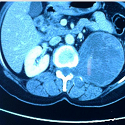

Masse rétro péritonéale kystique et multi-cloisonnée: kyste hydatique ou tumeur nerveuse?

Pierlesky Elion Ossibi, Imane Kamaoui

PAMJ. 2014; 19: 131. Published 06 October 2014